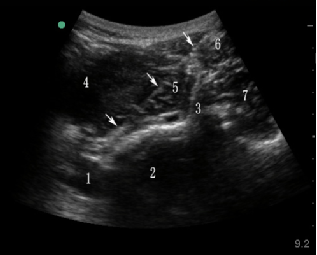

超声引导后入路腹腔神经丛阻滞超声图像

1.腹主动脉 2.腰2椎体 3.横突 4.肾脏

5.腰大肌 6.腰方肌 7.竖脊肌 箭头:穿刺针

病例一:63岁男性患者。因胰腺结石、慢性胰腺炎接受了胰管切开取石及胰管空肠吻合术,术后却遭遇上腰段持续性剧烈钝痛,持续时间长达三个月,VAS疼痛评分高达9分(0分为无痛,10分为剧痛),进食和睡眠受到严重影响。泰康医院疼痛科赵达强主任决定采用超声引导后入路腹腔神经丛阻滞来控制疼痛。然而,腹腔神经丛位于腹主动脉及其分支腹腔干周围,位置深邃,周围环绕着重要脏器,一旦损伤,可能引发并发症;而穿刺至血管,除了可能形成血肿,还可能导致截瘫、肺栓塞等严重后果。因此,穿刺过程中辨识这些结构,以及清晰显示穿刺针的路径,对于确保治疗效果和降低并发症风险至关重要。超声技术在此扮演了关键角色,它能够精确识别血管和重要脏器,并实时监控穿刺针的路径及注射药物的弥散情况,从而实现了精确穿刺至目标部位的同时,有意识地规避了重要器官。经过超声引导的腹腔神经丛阻滞治疗后,该患者的疼痛缓解程度超过50%,VAS疼痛评分降至3分以下,吗啡使用量大幅减少,进食和睡眠状况得到显著改善。